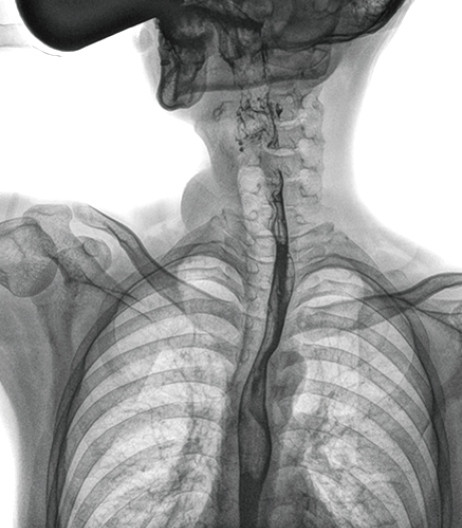

动态DR能够实现大幅面透视,瞬时高清点片等。在食管造影检查中,由于吞咽钡剂后,造影剂流速非???,在一个大幅面上方便观察食管的病变。瞬时点片,可以实时捕捉到病变部位的影像,从而可以快速做出诊断。普利德多功能动态DR拥有17×17英寸超大视野,一次曝光即可显示整个食管,更方便观察食管的病变,确定病变的范围,对诊断和治疗有重要参考价值。

与过去的数字胃肠机比较,动态DR图像分辨率高,对食管的全景观察,局部粘膜破坏、中断,管腔狭窄以及病灶范围的显示清晰度明显更优。

上消化道造影高清图像